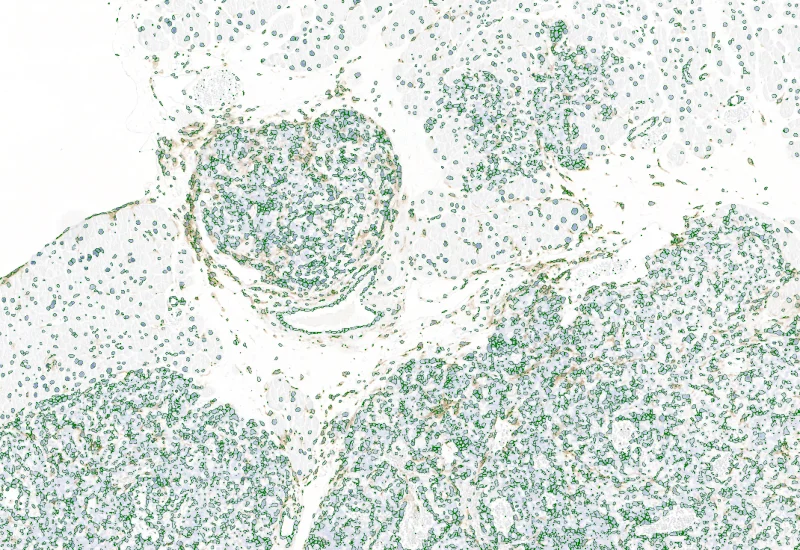

Nuclei detection

The IHC Tumor-Macrophages APP provides tissue detection including separation into tumor tissue and healthy tissue. It detects macrophages based on a specific staining (e.g. CD68). The APP outputs the area of macrophages within tumor tissue and healthy tissue.

Segment tissue into tumor and healthy areas, detect CD68+ macrophages, and quantify macrophage area within each tissue compartment.